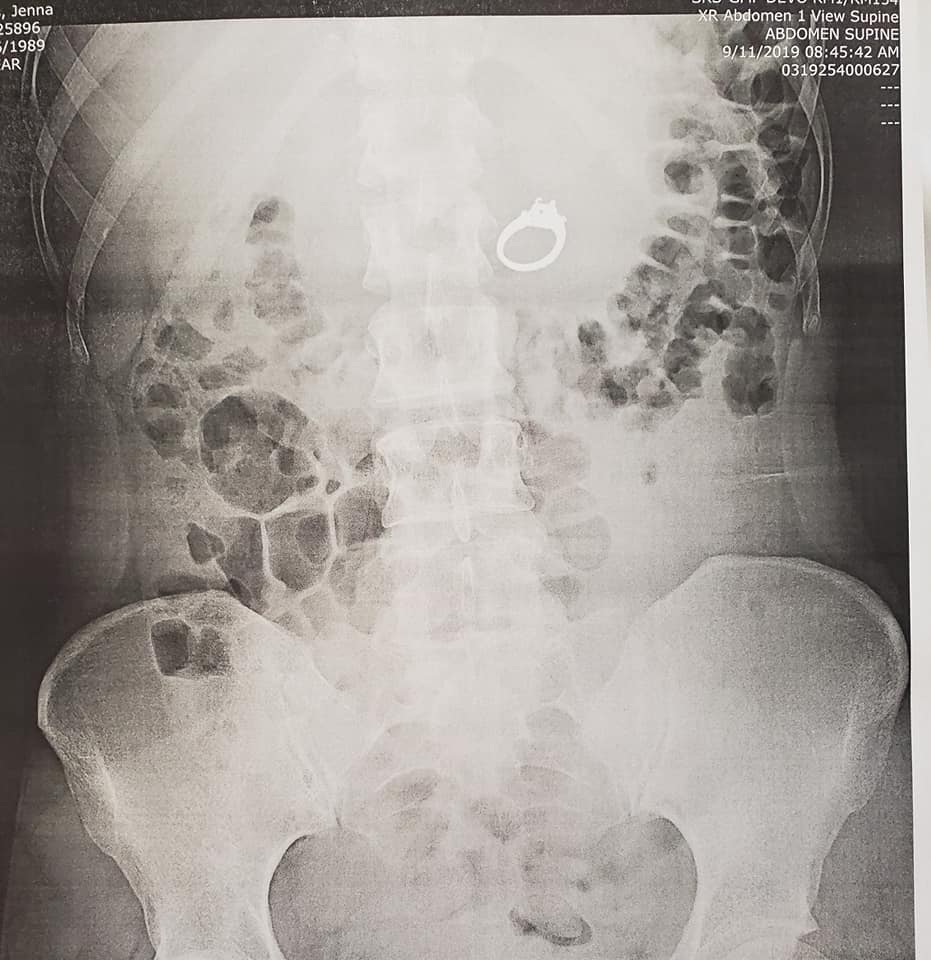

This Woman Swallowed Her Engagement Ring in Her Dream…And in Reality

Getting engaged is can be one of the highlights of a woman’s life. But one woman’s engagement went a bit awry when she accidentally swallowed her engagement ring in her sleep. It all started with a very strange dream. Jenna Evans dreamt that she and her fiancé Bobby were “in a very sketchy situation involving...